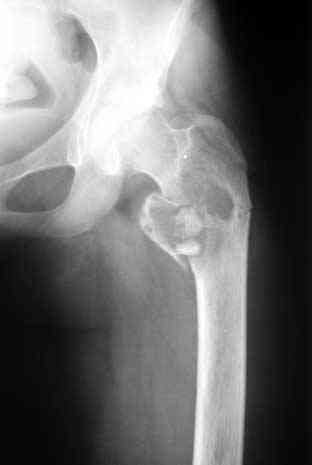

Под рукой нашелся повод для похожих эмоций. Патологический перелом на месте рецидива костной кисты у девочки 16 лет (обсуждали этот случай

года два назад). Ни коллапана, ни трансплантатов, ничего другого в очаг не вводили, кроме нержавеющей стали. Она, видимо, тоже остеоиндуктор - видно, что на месте пустоты через несколько месяцев кость.